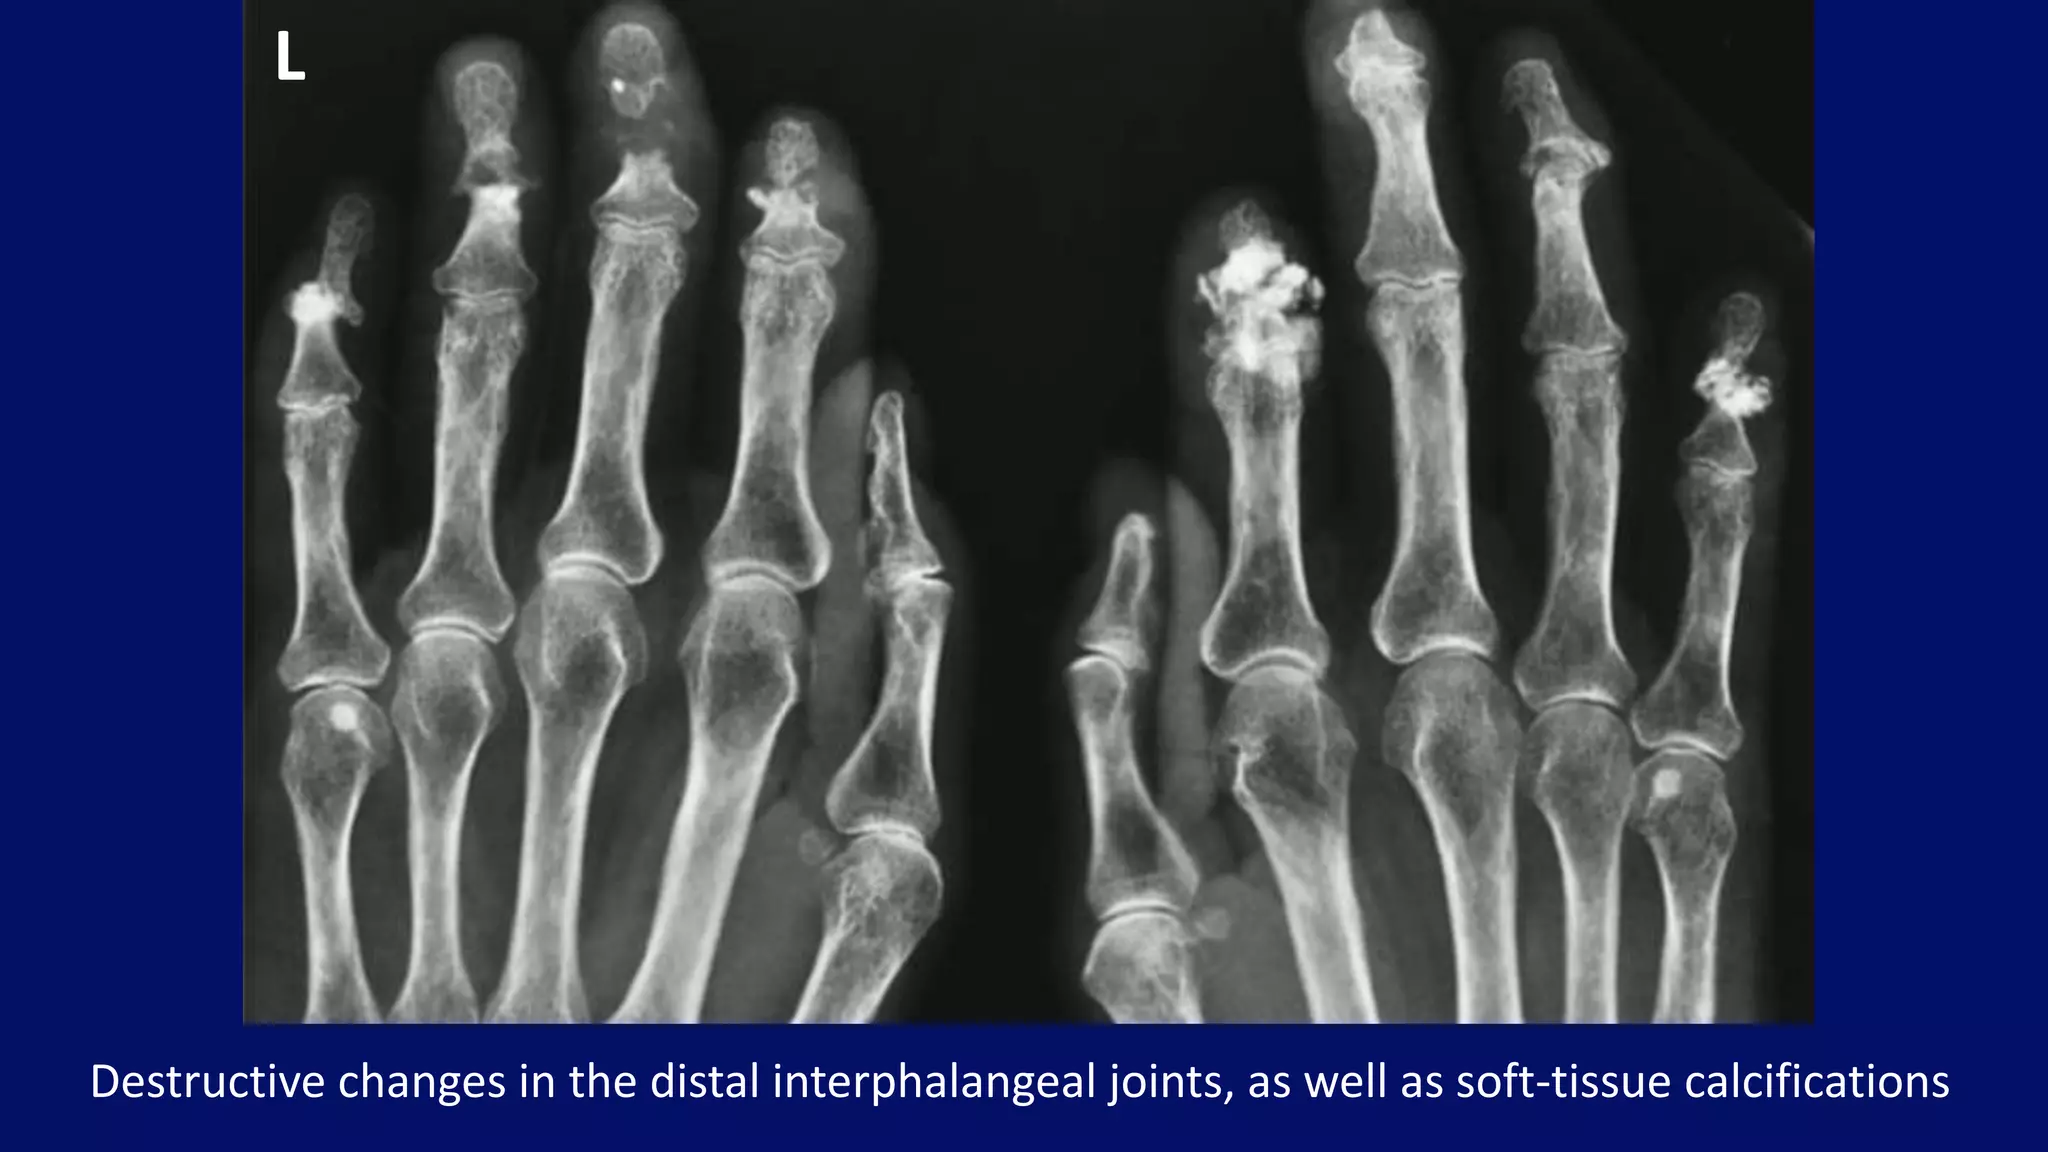

Destructive changes in the distal interphalangeal joints, as well as soft-tissue calcifications

L

• subcutaneous and periarticular calcifications

• destructive changes of the small articulations

Radiographic features